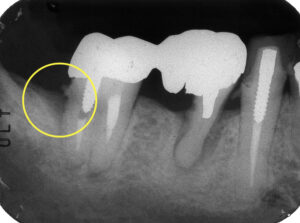

根管治療